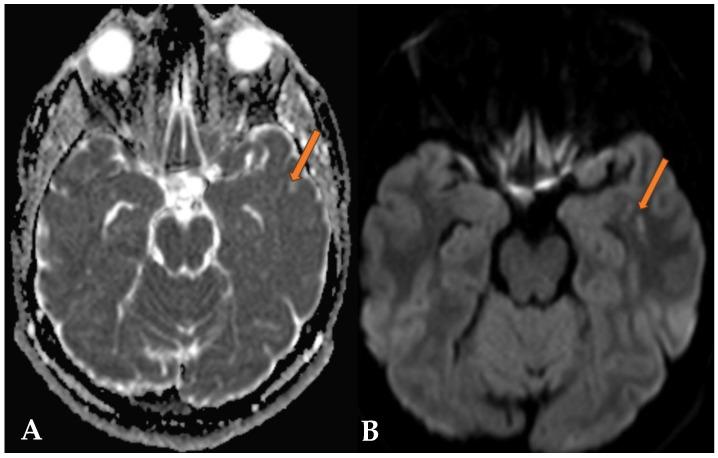

Multinodular Vacuolating Neuronal Tumors (MVNTs) are mixed glial-neuronal brain lesions classified as World Health Organization (WHO) CNS grade 1 tumors, often associated with long-term epilepsy. First described by Huse et al. in 2013 and included in the WHO CNS classification in 2016, MVNTs present a range of clinical manifestations, from symptomatic to asymptomatic. They typically affect young to middle-aged adults and exhibit diverse presentations. Radiologically, MVNTs are usually supratentorial, frequently located in the temporal lobe but also observed in the frontal and parietal lobes. MRI is essential for diagnosis, revealing multiple coalescing subcortical or cortical nodules with hyperintense signals on T2-weighted/FLAIR sequences, often without peripheral edema or mass effects. This paper presents two cases: one symptomatic MVNT with significant clinical manifestations, and the other documenting an incidental finding of MVNT in an asymptomatic patient. One case shows typical temporal lobe localization, while the other highlights a rare frontal lobe localization, with clear radiological findings on T2/FLAIR sequences. These cases illustrate the varied clinical presentations of MVNTs and emphasize MRI's critical role in diagnosis and management. Asymptomatic cases often require conservative management, stressing the avoidance of unnecessary invasive procedures and the importance of regular monitoring.

多结节空泡状神经元肿瘤(MVNTs)是一种神经胶质-神经元混合性脑病变,被归类为世界卫生组织(WHO)中枢神经系统1级肿瘤,常与长期癫痫相关。MVNTs于2013年由胡斯等人首次描述,并于2016年被纳入WHO中枢神经系统分类,其临床表现多样,从有症状到无症状。它们通常影响年轻至中年成年人,表现形式多样。在影像学上,MVNTs通常位于幕上,常位于颞叶,但也可见于额叶和顶叶。磁共振成像(MRI)对诊断至关重要,显示在T2加权/液体衰减反转恢复(FLAIR)序列上有多个融合的皮质下或皮质结节,信号增强,通常无周围水肿或占位效应。本文介绍了两例病例:一例是有明显临床表现的有症状MVNT,另一例记录了在一名无症状患者中偶然发现的MVNT。一例显示典型的颞叶定位,另一例突出了罕见的额叶定位,在T2/FLAIR序列上有明确的影像学表现。这些病例说明了MVNTs的不同临床表现,并强调了MRI在诊断和管理中的关键作用。无症状病例通常需要保守治疗,强调避免不必要的侵入性手术以及定期监测的重要性。